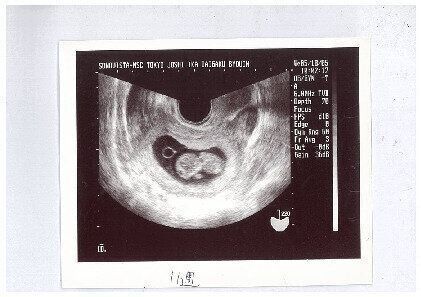

3. 妊娠初期の超音波検査で確認できることは?赤ちゃんの性別はいつごろわかる?【産婦人科医】